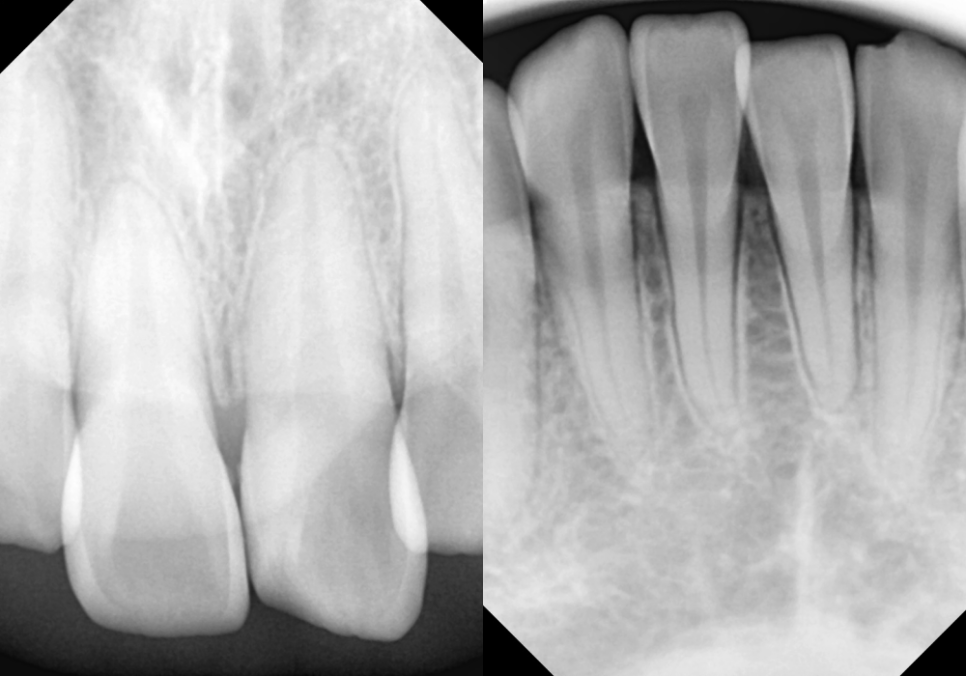

촬영일 : 24.01.09

치근단 엑스레이를 촬영해 보았을 때

치근의 길이가 양호하였기에

다음과 같은 진료를 진행하기로 했습니다.